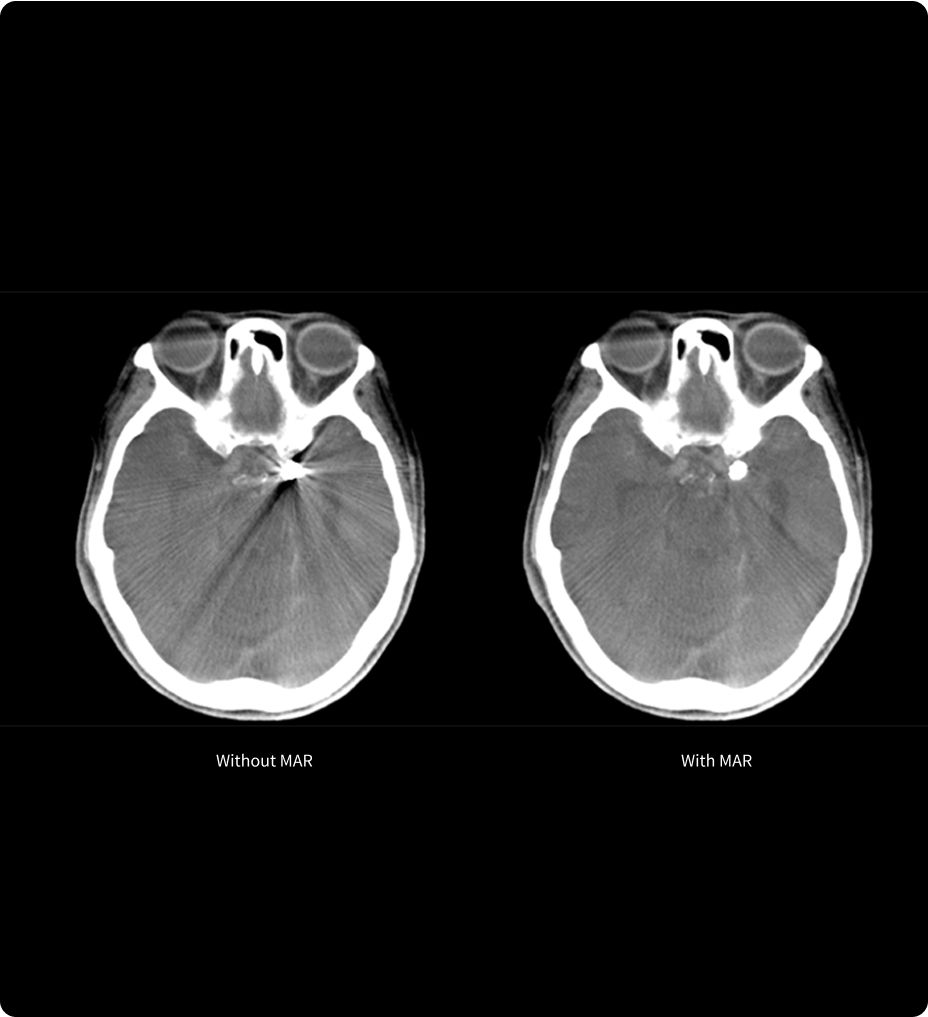

MAR11

Reduzierung von Metallartefakten, Optimierung der Bildqualität

MAR11 (Metallic Artifact Reduction, Metallartefaktreduktion) ist eine fortschrittliche Technologie zur Reduzierung von Artefakten, die durch Metallgegenstände im Körper, zum Beispiel Implantate, verursacht werden. Diese Artefakte können wichtige anatomische Details verdecken. Dies erschwert es dem Klinikteam, Diagnosen zu stellen und Behandlungen genau zu planen.

MAR11 gewährleistet eine verbesserte Bildqualität und ist demnach ein wertvolles Instrument zur Verbesserung der Genauigkeit und Sicherheit minimalinvasiver Verfahren.

feature-4